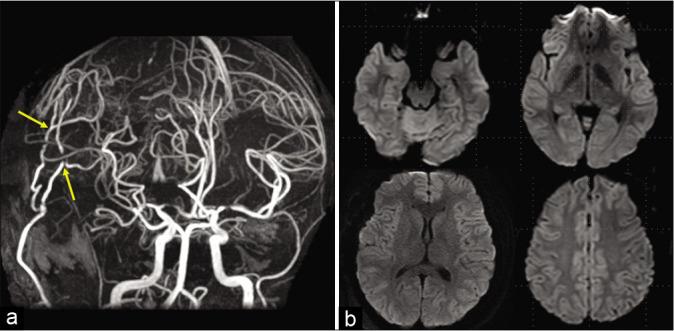

A 16-year-old girl presented with transient left upper and lower limb numbness and headache. Based on digital subtraction angiography, she was diagnosed with symptomatic moyamoya disease. Single-photon emission computed tomography (SPECT) showed decreased cerebral blood flow (CBF) on the right side, and she underwent direct and indirect bypasses on this side. Involuntary movements appeared in her right upper limb immediately postoperatively. SPECT showed decreased CBF to the bilateral frontal lobes. Subsequently, the patient was diagnosed with limb-shaking syndrome. After performing left-hemispheric revascularisation, the patient's symptoms resolved, and SPECT imaging confirmed improvements in CBF to the bilateral frontal lobes.

一名16岁女孩出现短暂的左上肢和下肢麻木及头痛。基于数字减影血管造影,她被诊断为症状性烟雾病。单光子发射计算机断层扫描(SPECT)显示右侧脑血流量(CBF)降低,她接受了右侧的直接和间接搭桥手术。术后立即在她的右上肢出现了不自主运动。SPECT显示双侧额叶的CBF降低。随后,该患者被诊断为肢体抖动综合征。在进行左半球血管重建后,患者的症状得到缓解,SPECT成像证实双侧额叶的CBF有所改善。